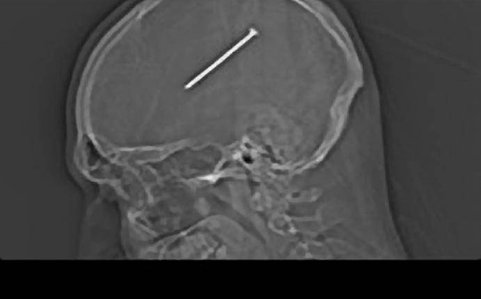

Stiri din pistol